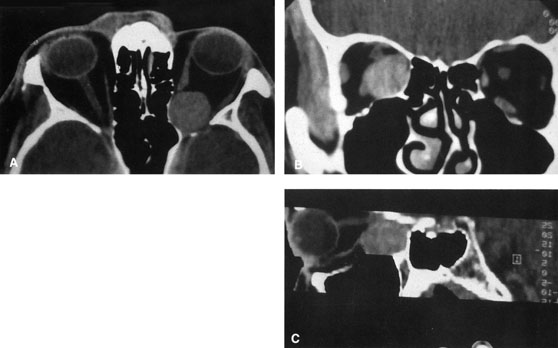

Fig. 6. Lateral orbitotomy through upper eyelid skin crease A. Photo demonstrating right globe ptosis present for more than 2 years. B. Axial CT scan showing a well outlined oval lesion in the lacrimal gland

fossa. C. Coronal CT showing lesion pushing globe inferiorly. D. Skin crease excision marked for lateral orbitotomy. E. Lateral orbital rim exposed. Bone cuts made above frontozygomatic suture

and at zygomatic arch. F. Lateral wall removed. Subperiosteal space exposed. Hard tumor could be

palpated in area of lacrimal gland. G. Benign mixed tumor of lacrimal gland removed. H. Bone sutured into place. I. Skin crease closed. |